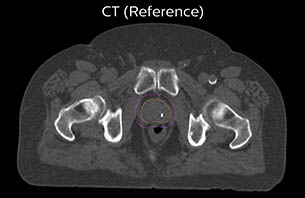

A 77-year-old male with prostate cancer cT3aN0M0, Gleason 8 and PSA 52 μg/L referred to androgen deprivation and radiation therapy with a prescribed dose of 50 Gy to the pelvic lymph node regions and 76 Gy to the prostate.

The 3D T1W FFE mDIXON sequence provides in-phase, water and fat images in one acquisition. Target and organs-at-risk are delineated on the 3D T2W TSE images. Prostate GTV is shown in orange, PTV in purple. The 3D bFFE sequence is used by the planner to mark the position of the fiducial markers (gold anchors) and contours are transferred to the digitally reconstructed radiographs (DRRs).

Based on the 3D T1W mDIXON images, MR-based density maps (MRCAT) are automatically generated. The VMAT (Volumetric Modulated Arc Therapy) plan is generated in TPS, based on MRCAT as primary image set. During the commissioning phase, dosimetric agreement between MRCAT-based and CT-based dose plans was studied and differences in the PTV dose were found to be minimal (<1% for most patients). Average difference in PTV mean values was 0.8% over the study group (n=62).